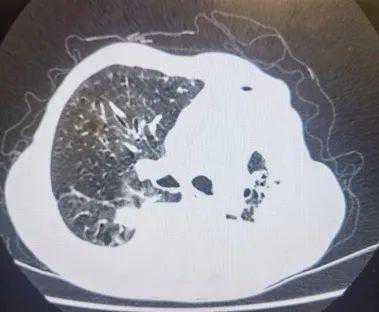

屠老伯因胸闷就诊,发现左侧大量胸腔积液收治我科,胸水反复送检仅见“少量腺样上皮细胞异形”,胸部CT提示“左侧胸腔积液,左侧支气管局部轻度狭窄,左肺局部实变不张,不排除肿瘤“。为尽早明确诊断,我们进行了电子支气管镜检查。然而,支气管管腔内并未见新生物、狭窄等,于是,我们用超声小探头一探究竟——超声小探头进入屠老伯左下肺背段的亚段支气管后缓慢移动,当细雪花样声像图中出现了岛屿样的轮廓时,我们知道已经缉拿到肿块了!顺利地进行了刷检、活检及灌洗后,屠老伯安返病房。